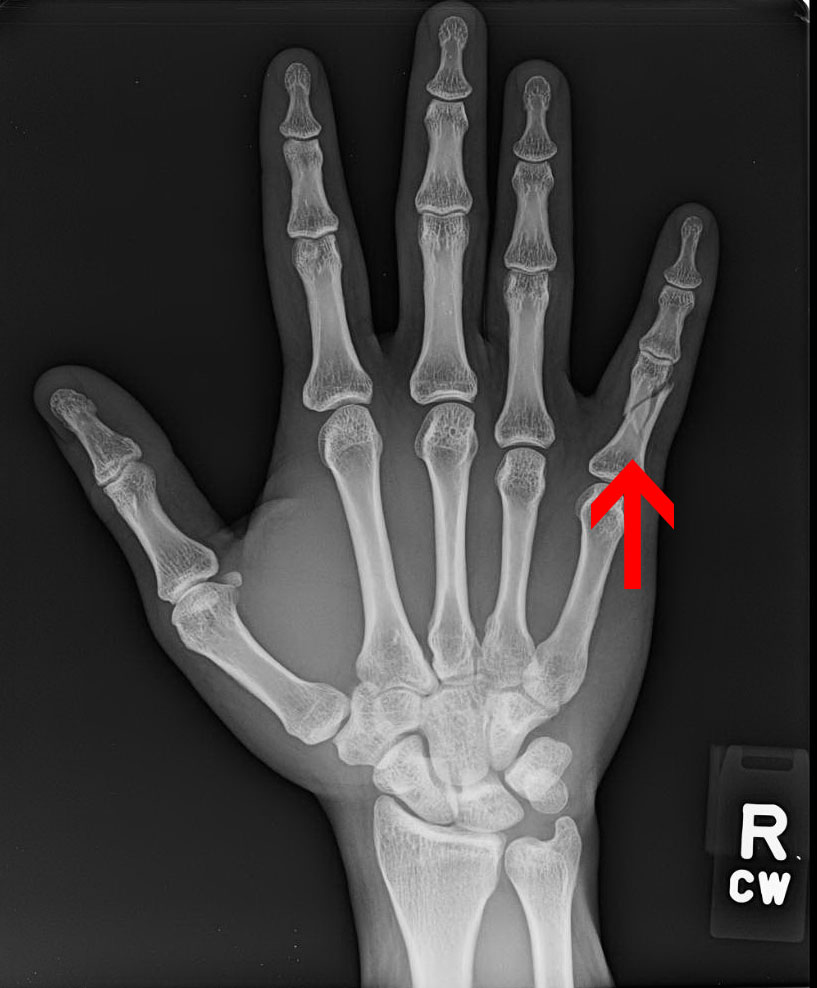

Dacă îmi fracturez degetul mic, am nevoie să mă eliberez de un aspect al vieții mele, posibil legat de autoritate.

Poate fi, de asemenea, un secret pe care îl port de mult timp și care mă roade în interior.